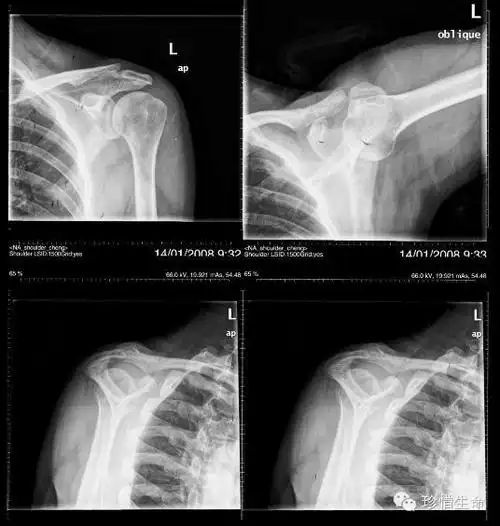

肩部背部外伤要注意肩胛骨,肩关节正位不宜观察,可以结合斜位,最好ct

遇到肩部外伤时肩关节ct有必要做吗